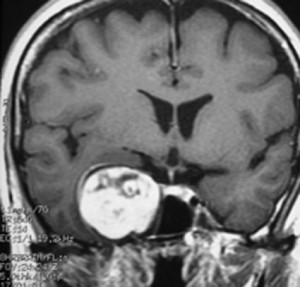

特殊な蔓状三叉神経鞘腫

NF-1ではない孤発例の三叉神経蔦状神経鞘腫です。眼窩内,上眼窩裂,メッケル腔,小脳橋角槽まで伸びる大きなものです。内視鏡の手術はできないので,開頭手術になりますが,全部まとめて摘出できます。